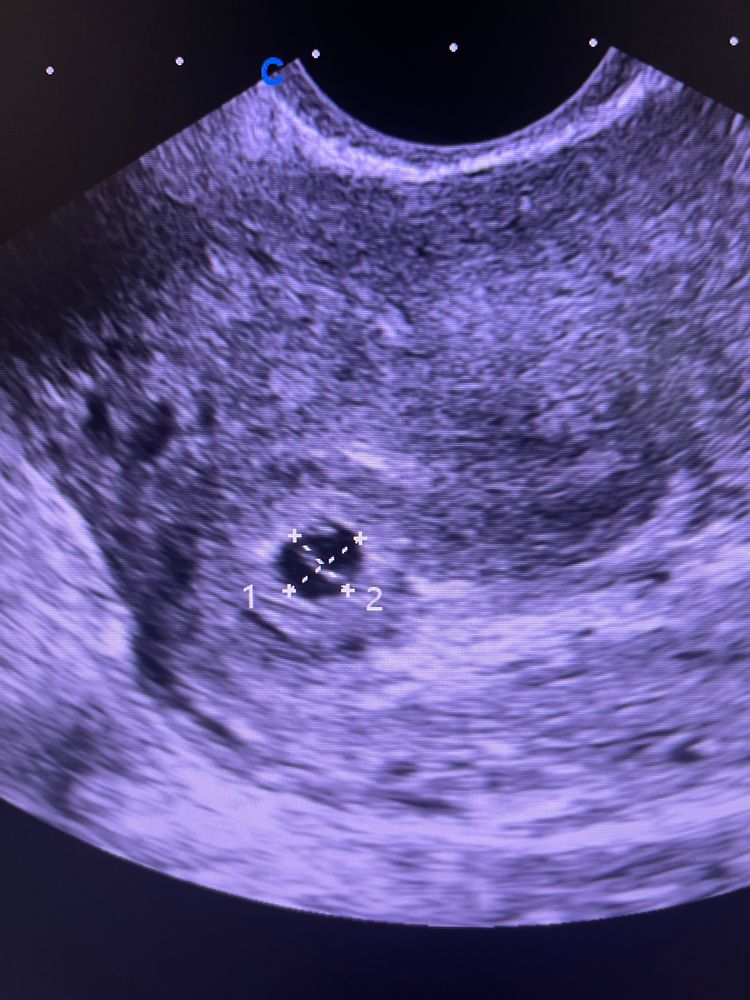

Результаты УЗИСегодня было первое узи

20 дпп .

я особо не понимаю ,но вроде все в порядке )